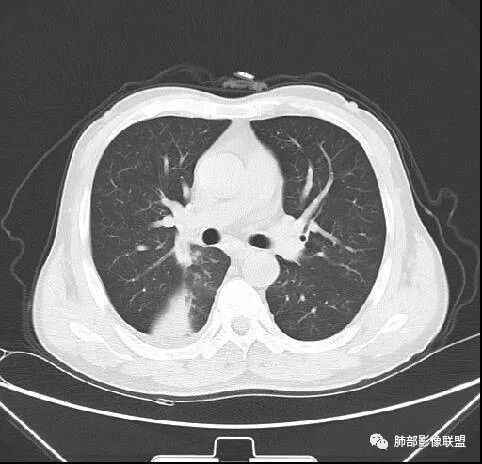

南边:紧贴着斜裂过来的一个病灶,它的特点是:外围大,内带小。它整个下叶背段体积与对侧相比稍微缩小一点,但是缩小地不是很厉害。外支朝前下走了,仔细看血管,肺动脉走行自然,直达远端。远端实变区是肉芽肿成分,稍微有一点低密度,没有明显坏死,稍微有一点点坏死。而且附近有很多卫星灶,附近很多斑片影,有一些明显有气道壁增厚,细支气管炎的特点,还有就是下叶其他段很多斑片状影。换个角度,第一如果是肺癌,刚才看到PET-CT提示肺癌伴阻塞性肺炎,这个是不符合的。第二如果是肺癌阻塞性肺炎,近端血管肺动脉走行不会那么自然集聚的,这个是不符合的。理由是:如果这个病灶是肺癌,那么明显属于中央型肺癌,中央型肺癌的特点是近端大,远端小,近端是一个肿块,远端阻塞,远端阻塞是阻塞性炎症或者不张,它应该体积缩小,斑片状实变,不会这么密实。刚才有老师提到支气管,这个片有缺陷的地方,给的图像好像那层,如果把其他图像拿开再重叠一下。

南边:这个肺门区,11区和7区都有一些淋巴结,淋巴结的形态不是类圆形,而是梭形的。这个病灶给的图比较少,个人倾向,第一强化非常均匀,肉芽肿性病变;第二,里面血管走行非常自然,远端大近端小,倾向炎性,特别是下面还有斑片状影,非阻塞远端,支气管远端病灶下叶背段,其他段也有,所以我倾向炎性;另外,它里面整个走行符合支气管树爬行征,我倾向结核可能,首先我定在炎性,其次有没有结核的可能。

鉴别诊断:肺炎性肺癌,胸膜下起源,外围大,局部占位效应,有膨隆有收缩,这个不太支持。支气管走行里面没有看到支气管进入很自然堵塞的粘液栓的特点。附近这些磨玻璃影,它的磨玻璃影要么边界清楚,要么由内朝外蔓延的,而不是沿着支气管束蔓延的。而且附近斑片状影,有些似乎有结节感,但是大部分不是,它不是我们常见的磨玻璃样结节,有些有,导致像腺泡样结节那种椭圆的沿着血管束分布的,我会把肺炎型肺癌放在待排。

右肺下叶背断肿块,外围大,内带相对狭长         远端有膨隆,边缘模糊、凹凸不平         血管走形自然,病灶近端支气管通畅,沿支气管树蔓延         周边有多发病灶,多为磨玻璃密度且边界不清。